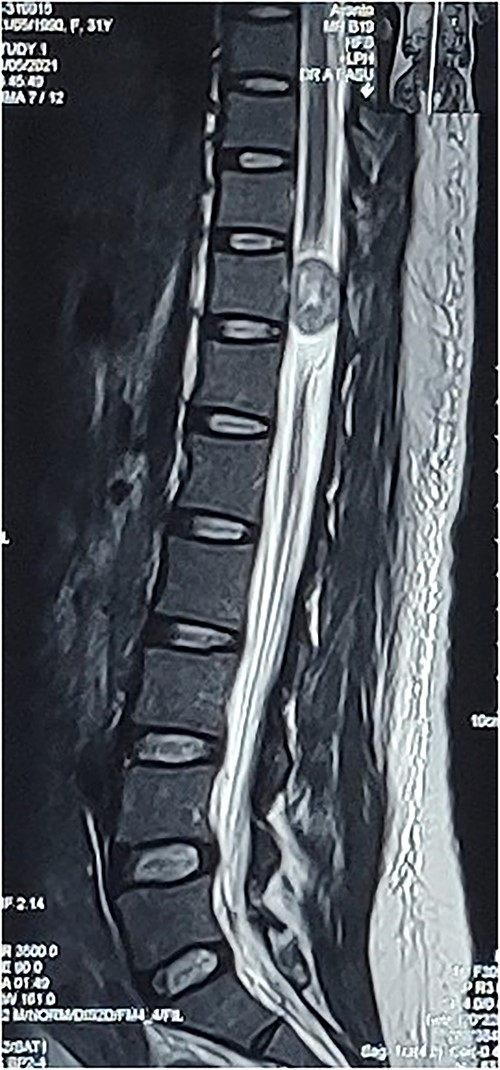

A 31-year-old post-partum female presented with acute onset paraparesis on the third day following uneventful caesarean delivery under combined spinal epidural anaesthesia. The patient was referred to our hospital 1 week after delivery with Grade 2 power in left lower limb and Grade 3+ power in right lower limb. There was graded sensory loss below D12 level. Lower limb deep tendon reflexes were exaggerated and bilateral plantar reflexes were extensor. Bladder and bowel were not involved. MAS Grade 1 spasticity was seen in bilateral lower limbs. MRI revealed an ovoid solid lesion behind the D11 vertebral body, which was hypointense in T1W and hyperintense on T2W images (Fig. 1). The following day, she underwent a dorsal laminectomy (D10–11) and the excision of the tumour without any instrumentation. The patient recovered uneventfully from the surgery and had rapid improvement in lower limb muscle strength. On discharge, the patient was independently ambulatory and had Grade 4/5 power in bilateral lower limb. She had improvement in sensation following surgery. On 3-month follow-up, the patient had full motor recovery and was able to walk independently. A repeat MRI showed no residual tumour.

Preop sagittal T2W image showing hyperintense SOL consistent with schwannoma.